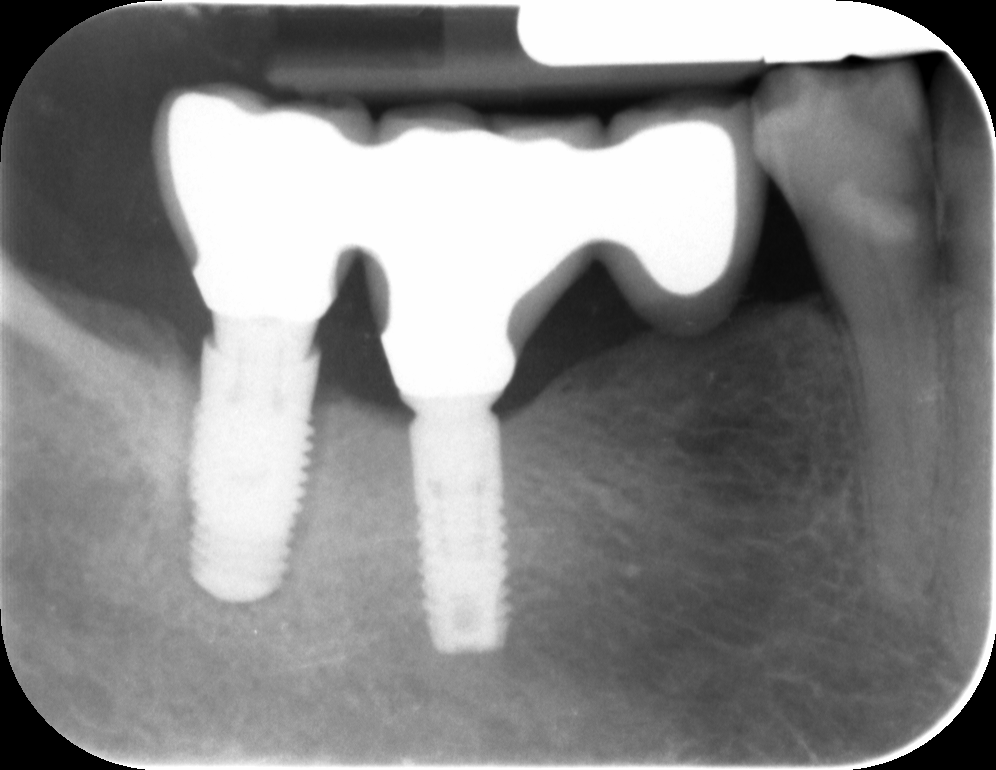

Estos implantes llevan varios años en boca, completamente oseointegrados, pero necesitamos sustituir la prótesis por razones oclusales e higiénicas, ya que tienen una emergencia gingival en silla de montar absolutamente [...]